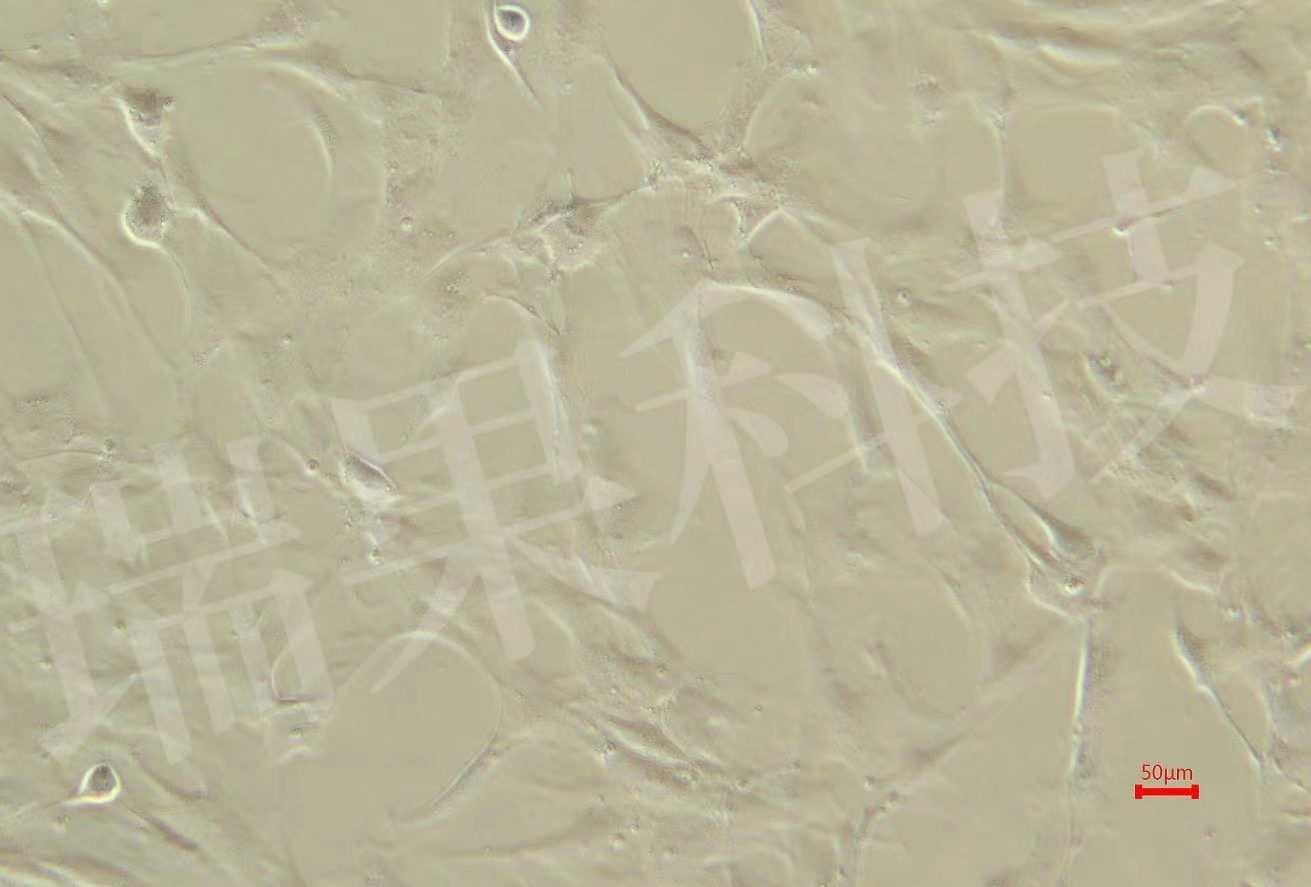

• 糖尿病肾病模型

提供系统的糖尿病肾病动物模型构建与表型分析服务,涵盖模型选...

糖尿病肾病模型